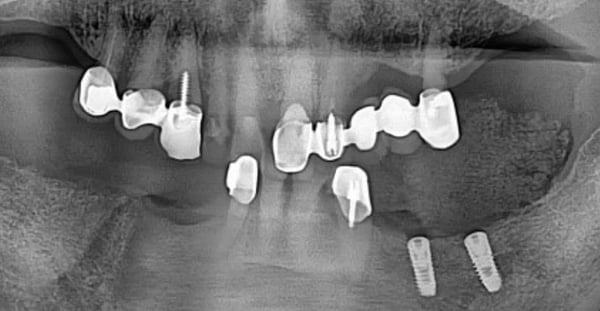

但在擁有完整數位工作流的診所裡,這卻是一個展示應變能力的絕佳時刻。Dr. Lee 迅速調整策略,決定提早啟動右側的治療,並大膽採用「導引式手術」搭配「立即受力」。這意味著病患將在手術當天就獲得固定的臨時贋復物,徹底告別活動假牙的夢魘。

要實現這個大膽的計畫,精準度是唯一的依歸。這裡展現了一個極具價值的臨床技巧:在進行 CT 與口內掃描檔案的疊合時,由於病患口內缺乏足夠的自然牙作為特徵點,且金屬假牙在 CT 上會產生散射干擾,Dr. Lee 巧妙地在牙齦上放置了標記物。這些標記物就像是茫茫大海中的燈塔,讓 Implant Studio 軟體能完美地將骨骼資訊與軟組織資訊鎖定在一起。

手術現場:不翻瓣與立即受力的精準演繹

手術當天,數位規劃的價值轉化為實質的臨床紅利。由於術前已透過軟體精確計算了植體位置與角度,Dr. Lee 得以執行不翻瓣手術。手術導板與牙齦的密合度極佳,無需額外的骨釘固定,手術過程安靜、快速且出血量極低。這對於病患來說,不再是一場血淋淋的手術,而是一次精密的醫療體驗。

經過兩個月的癒合期,從 X 光片中可以清晰看見,即便經歷了立即受力,植體周圍的邊緣骨依然穩定,毫無吸收跡象。這證明了數位導引手術在分散咬合力上的卓越表現。最終,醫師利用已經確認穩定的咬合記錄,透過數位印模製作了全鋯冠。當最終贋復物裝在病患口中,那種絲毫不差的密合度與無需反覆修磨的順暢感,正是數位全口重建最迷人的終點。